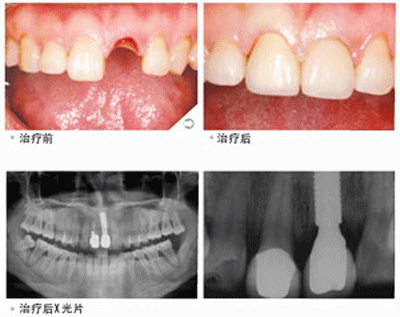

什么是种植牙?

医生介绍,种植牙也叫人工种植牙,是通过医学方式,将与人体骨质兼容性高的纯钛金属经过精密的设计,制造成类似牙根的圆柱体或其他形状,以外科小手术的方式植入缺牙区的牙槽骨内,经过 1~3 个月后,当人工牙根与牙槽骨密合后,再在人工牙根上制作烤瓷牙冠。因不具破坏性,种植牙已被口腔医学界公认为缺牙的首选修复方式。